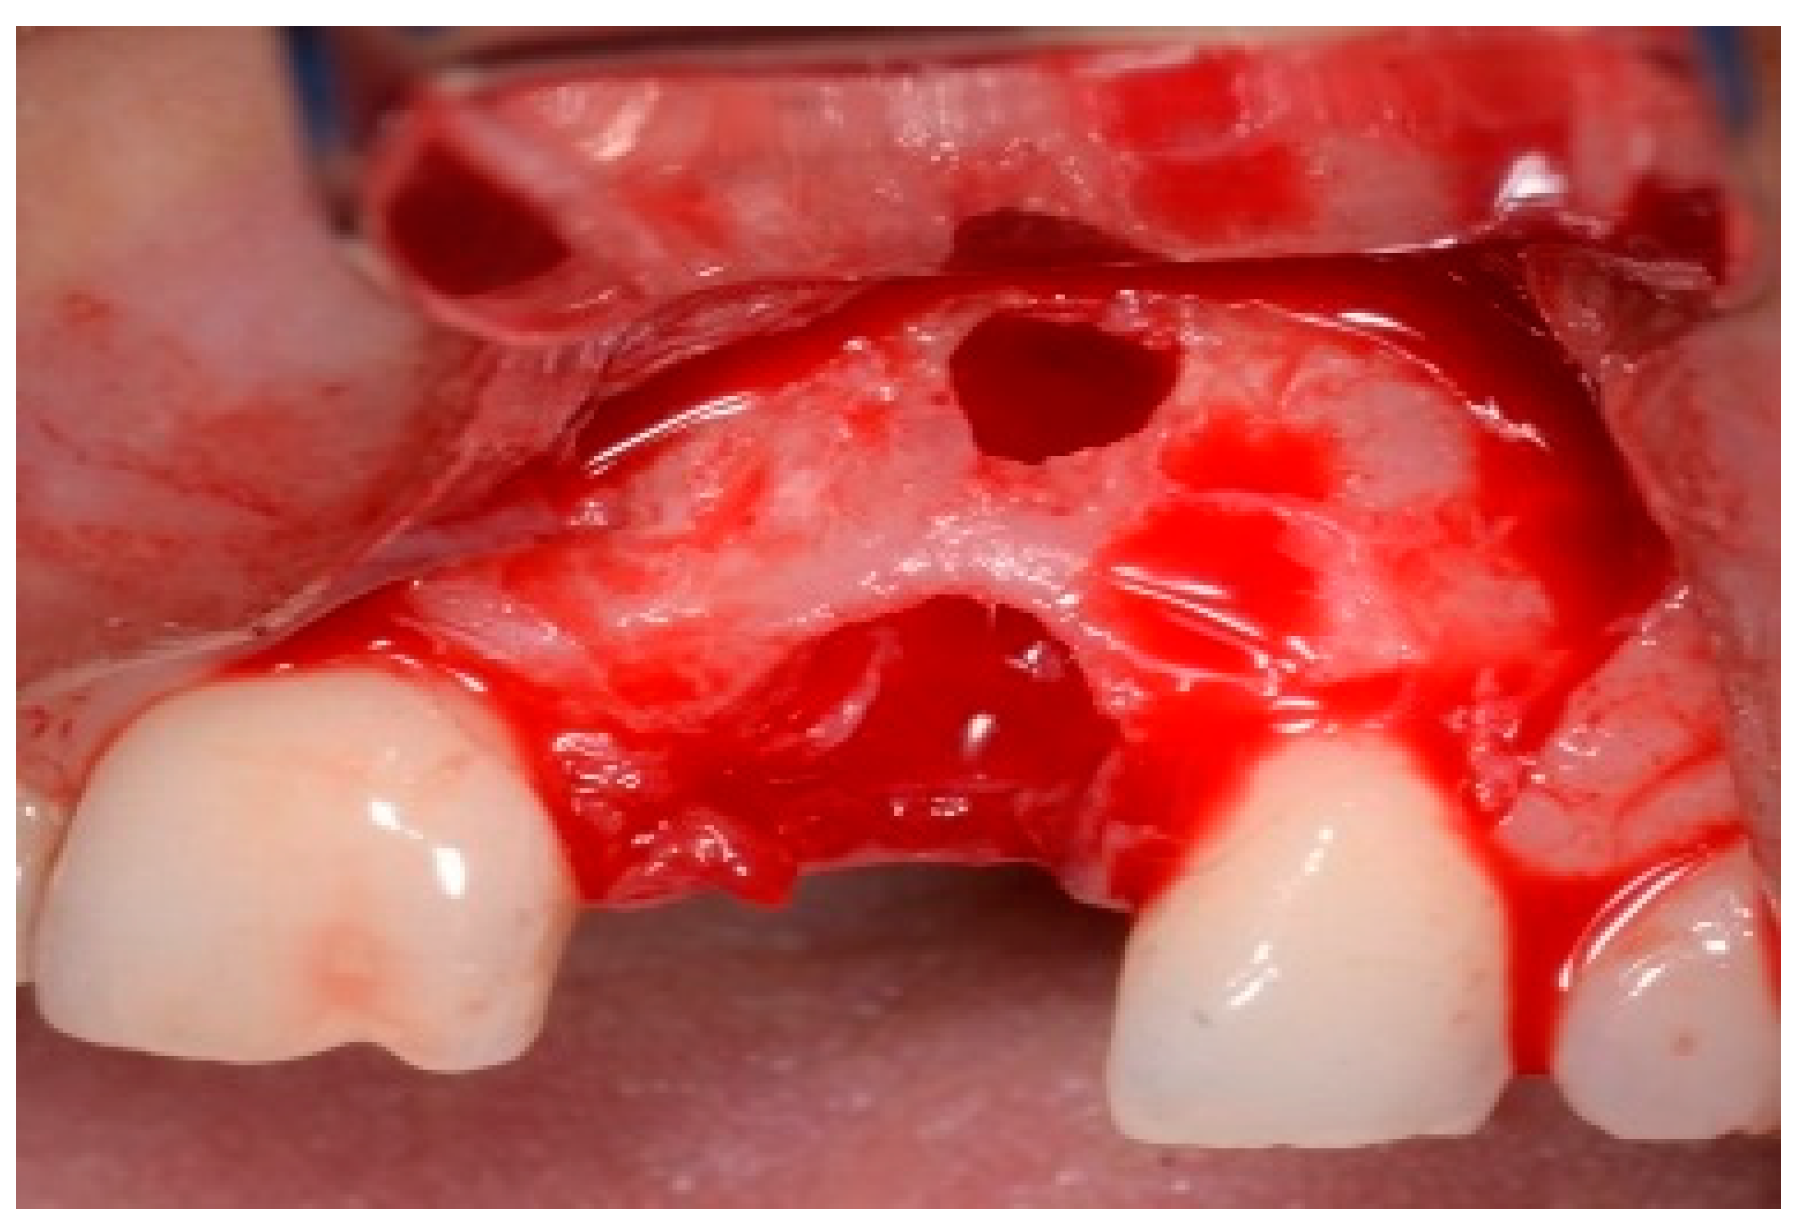

The patient accepted the proposed treatment plan. The preoperative surgical protocol described in patient 1 was followed. An L-shaped aesthetic flap design was chosen to treat this case. The flap started with an incision extending from the distal line angle of the central incisor to the mesial line angle of the canine. A vertical incision was carried out past the mucogingival junction, followed by the elevation of a full-thickness flap. The remaining tooth root was extracted, maintaining the existing facial bone (Figure 9).

Figure 9.

Clinical view of implant replacing.